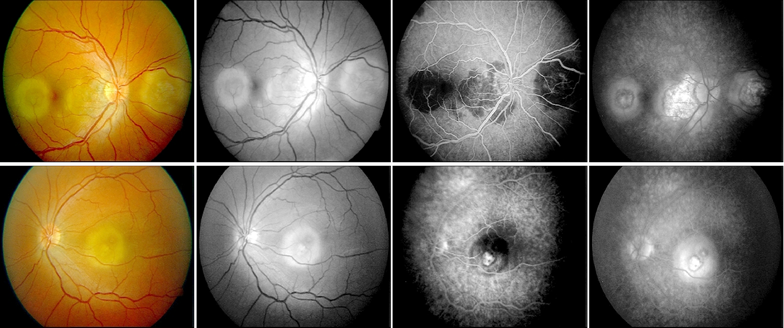

Color fundus photographs of the right eye showed a contiguous peripapillary geographic lesion with multifocal gray-yellow placoid lesions extending temporally, while the left eye demonstrated a solitary fovea-centered placoid lesion (Figure 1).

Figure 1. Fundus photographs and fluorescein angiography at presentation showing peripapillary and macular lesions.

Upper raw figures represent the right eye, lower raw images represent left eye.

Fluorescein angiography revealed early hypofluorescence of active lesions with late staining at the margins, consistent with serpiginoid inflammatory activity. At the time of presentation, optical coherence tomography (OCT), fundus autofluorescence (FAF), and indocyanine green angiography (ICGA) were not available at our institution; therefore, imaging assessment was limited to color fundus photography and fluorescein angiography. ICGA can delineate choroidal non‑perfusion and occult active margins (5,7–9). Follow-up fundus photography at six months demonstrated stable chorioretinal scarring without evidence of lesion progression or recurrence (Figure 2).